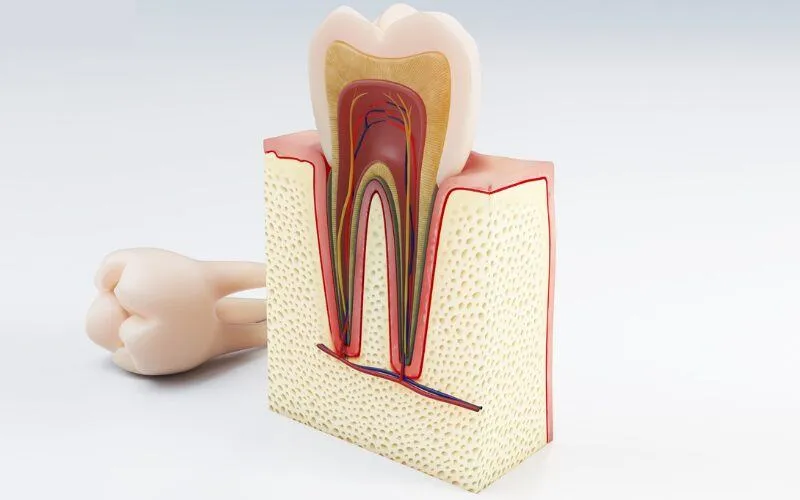

Sâu răng có thể dẫn tới các tình trạng viêm tủy ở nhiều cấp độ nguy hiểm nếu không kịp thời phát hiện và điều trị. Viêm

Hàn ống tủy răng là kỹ thuật nha khoa được nha sĩ chỉ định trong các trường hợp răng gặp vấn đề hoặc bệnh lý liên quan